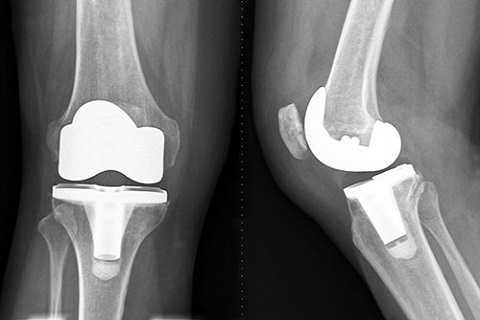

Artrosis

La artrosis es una enfermedad reumática crónica que lesiona el cartílago articular. Se produce fundamentalmente en las manos, las rodillas, la cadera y la columna cervical y lumbar..